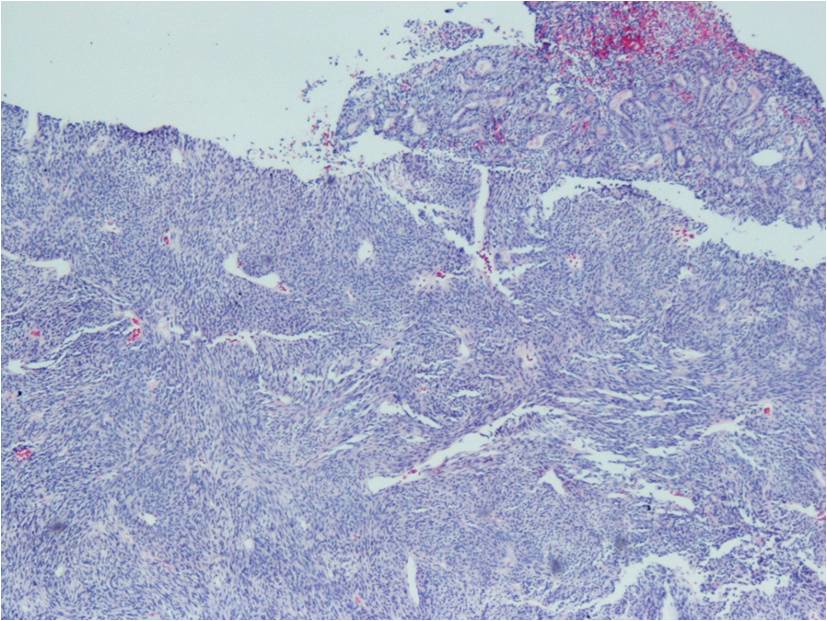

Biphasic form is composed of both epithelial-cell and spindle-cell components in equal proportions (Fig. 6-8)